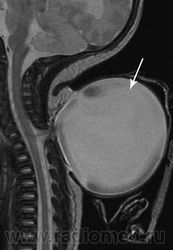

Менингоцеле

Приложения:

3.cover_.giff18.medium._meningocele..giff19.medium._meningocele..gif

Менингоцеле – выбухание в дефект позвоночника только оболочек спинного мозга. Грыжевое выпячивание просвечивает в проходящем свете, покрыто истонченной кожей с элементами атрофии, пигментными пятнами, оволосением. Менингоцеле достигает иногда огромных размеров, имеет ножку, при пункции спадается. Эта форма является наиболее доброкачественной из всех спинномозговых грыж, так как спинной мозг обычно сформирован правильно.